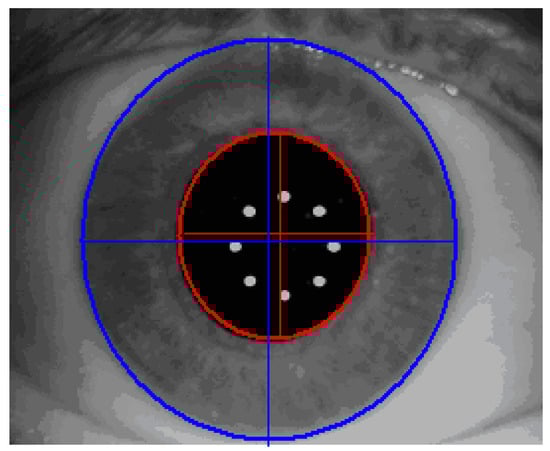

Certain sanity checks are applied to ensure that the automatically identified pupil and limbus geometries are within reasonable measures. The visible iris pattern defined as the structures between the pupil boundary and the limbus edge are used to create a normalized band (Figure 6).

Figure 6. Visible iris pattern definition.